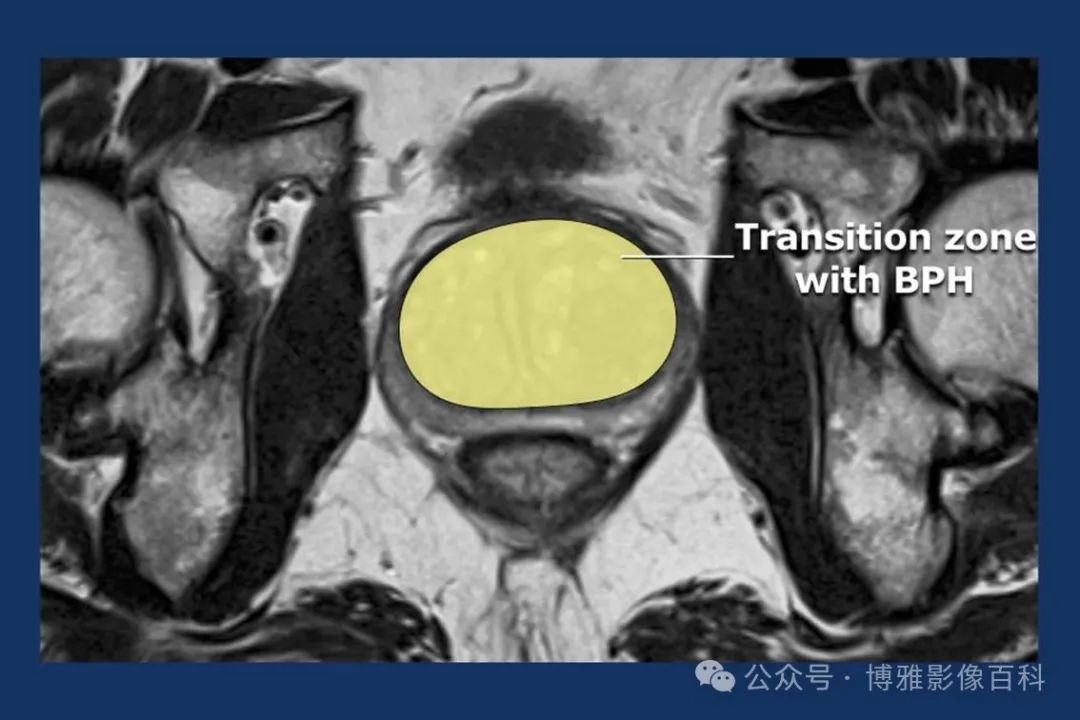

前列腺良性增生患者的轴向T2 图像,其他方面正常。外周带是一薄层均匀的高信号,边界清晰连续性的低信号包膜。移行带通常表现为不均匀中等信号,病灶被边界清楚的BPH良性前列腺增生结节所取代。精囊具有均匀T2高信号。未见淋巴结肿大。